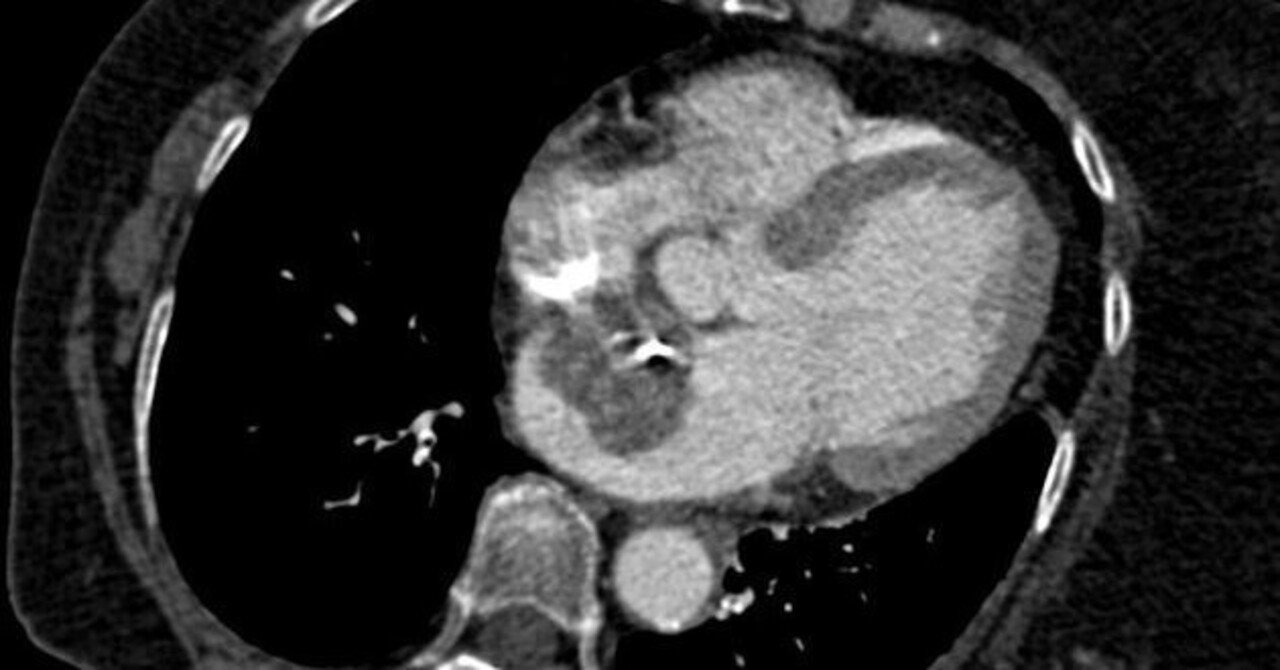

- 脳、胸部、腹部、骨盤、乳房の画像検査

診断には、脳、胸部、腹部、骨盤、乳房の画像検査や血液と尿の臨床検査など、さまざまな検査の実行が含まれる場合があります。